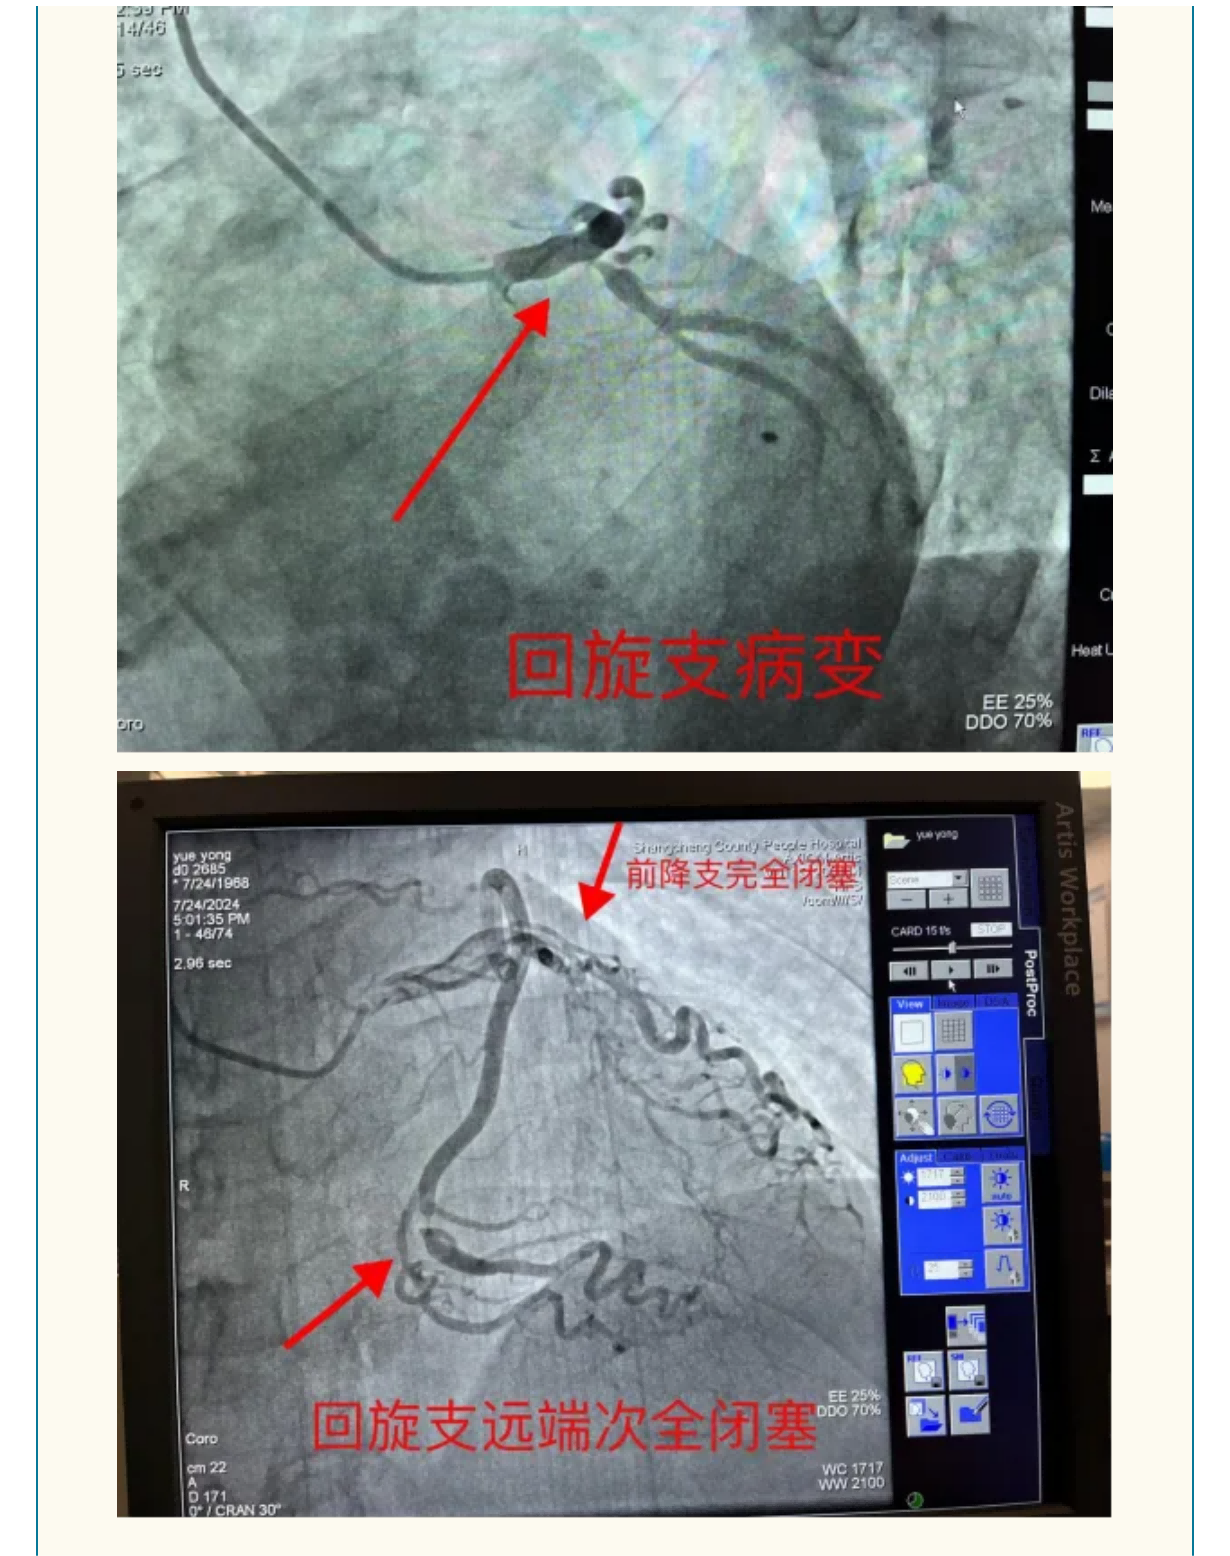

勇攀“心”高峰:我院心血管内科成功救治重症冠心病患者